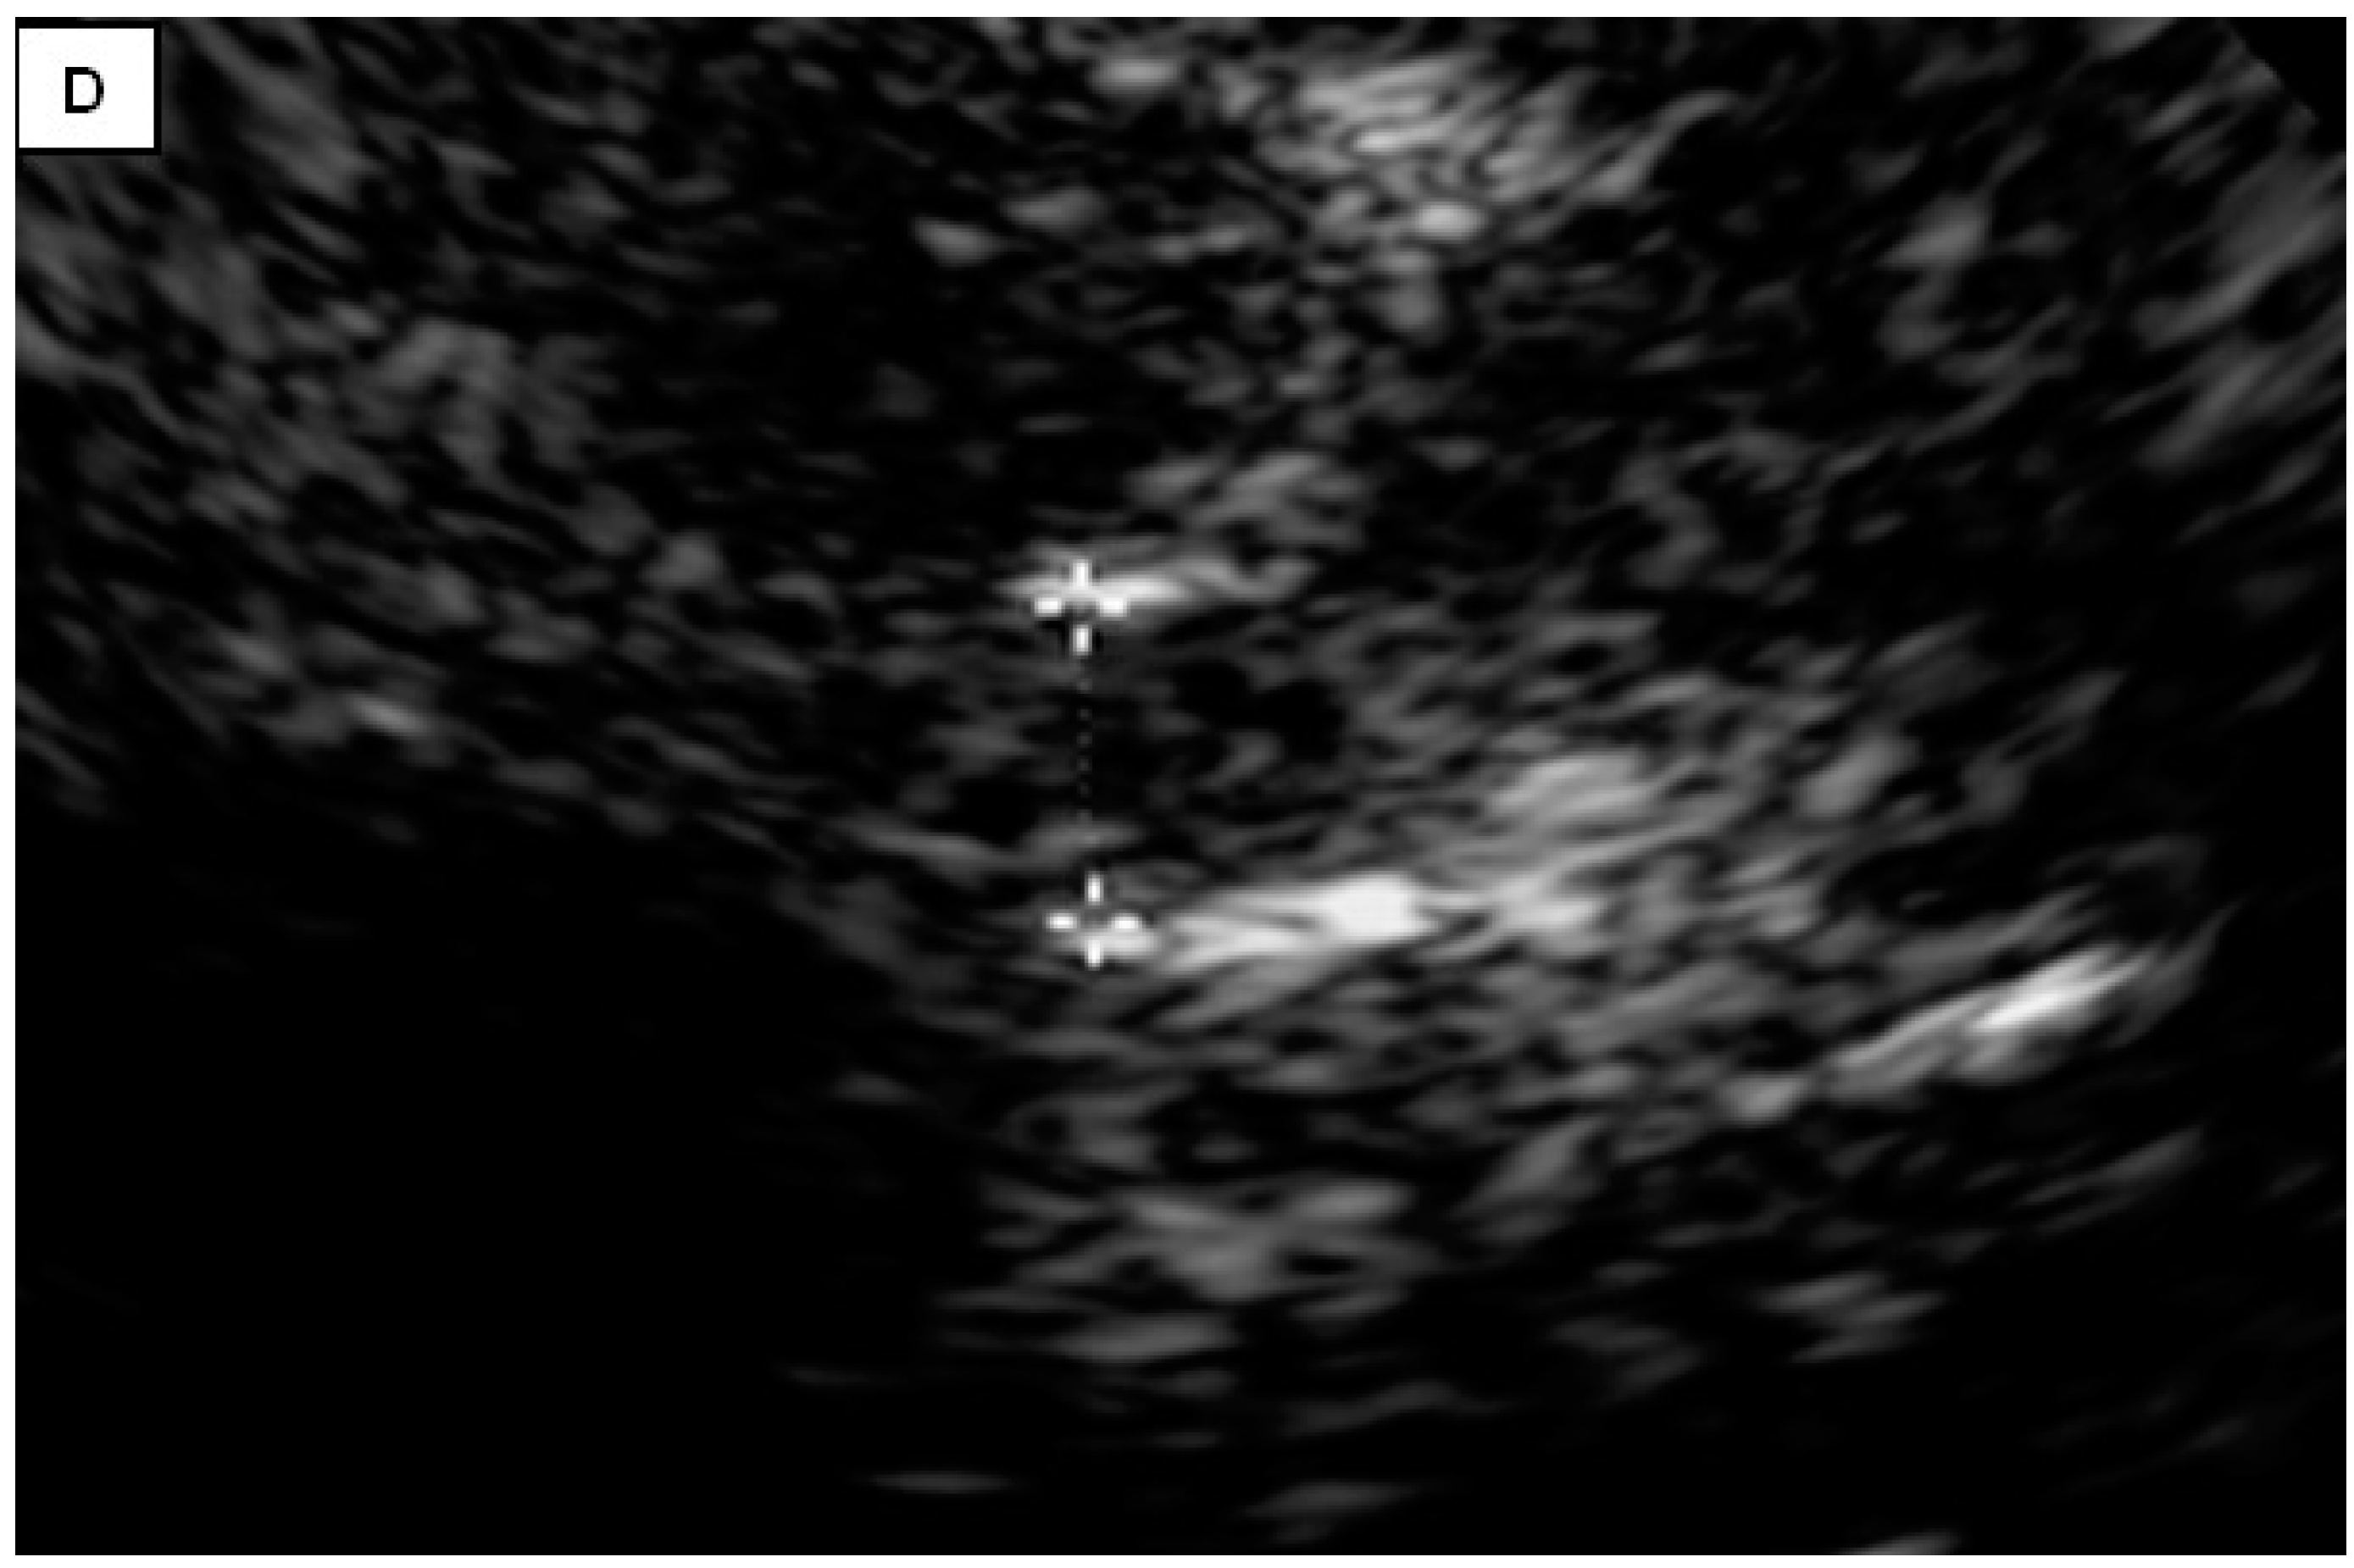

TCS characteristics of interest in our study are illustrated in Table 2. The control subjects consisted of 31 healthy controls, of which there was a slight female predominance (54.8%). The mean age of control subjects was 45.7 ± 11.6 years. The brainstem raphe was discontinued in 33.8% of patients. The SN hyperechogenicity was identified in 79.7% of patients, which represented a significant pathological finding, Figure 1. Third ventricle enlargement (over 6 mm) was present in 79.7% of patients, which can be attributed to gross (whole) brain atrophy, Figure 1. The fourth ventricle was enlarged in 45.9% of patients, which can directly be attributed to the atrophy of the cerebellum and its reduction in volume. The hyperechogenicity of other brain structures, such as the NR, the lentiform nucleus (NL) and the dentate nucleus (ND), is also illustrated in Table 2. We found a statistically significant difference in the hyperechogenicity of SN on the left and the sum quantitively, as well as in the frequencies of hyperintensity between patients with degenerative ataxias and the control subjects (p < 0.05). We have also found statistical significance in the difference between these two groups in the domain of the III and IV ventricles (p < 0.01). Results of mesencephalic atrophy are also presented in Table 2.

Figure 1.

(A) Butterfly-shaped hypoechogenic mesencephalic brainstem insonation level. Normal echogenicity of the brainstem raphe (highly hyperechogenic continuous line, same echogenicity as red nucleus; red arrow); dotted like highly hyperechogenic red nucleus (NR) (yellow arrow); normal echogenicity of substantia nigra (SN) (white arrow). (B) Butterfly-shaped hypoechogenic mesencephalic brainstem insonation level. Hypoechogenic interrupted raphe (red arrow); hyperechogenic substantia nigra (SN) (blurred yellow area, above 0.19 cm2). (C) Third ventricle level insonation depicted as hyperechogenic parallel lines. Normal diameter of the third ventricle (inner borders marked with red line). (D) Third ventricle level insonation depicted as hyperechogenic parallel lines. Dilatated third ventricle (12 mm, inner borders marked with white asterisk).

A positive and strong statistically significant correlation (p < 0.01) was found between dystonia and SN hyperechogenicity. Also, a positive and strong statistically significant correlation was found (p < 0.05) between rigidity and dyskinesia and SN hyperechogenicity. Such results are illustrated in Table 3. The higher SARA total score is statistically significantly correlated with the larger diameter of the III (r = 0.373; p = 0.001) and IV ventricles (r = 0.324; p = 0.005). Discontinued raphe was statistically significantly associated with Hamilton depression score (r = −0.225; p = 0.054). However, it must be said that it is a threshold value; that is, the level of significance is about 5%, so it can be interpreted that there is a negative and statistically significant correlation between the two mentioned variables.